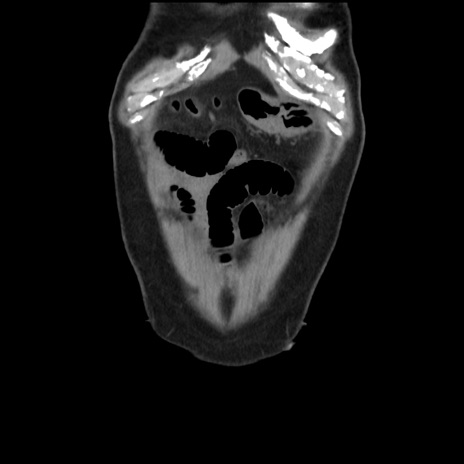

症例16(冠状断像)

【症例】 70歳代男性

【主訴】 腹痛、嘔吐

【現病歴】 約1ヶ月前より間欠的に腹痛と嘔吐あり、当院消化器内科を受診したところCTで多発する肝臓のLDAを指摘され、精査中であった。以降は消化器症状は安定していたが、2日前より嘔気と腹痛があり、同日より排便・排ガスが消失した。改善認めず、 本日、救急外来を受診した。

【身体所見】意識清明・会話良好、BT 36.3℃、BP 127/80mmHg、 P 80bpm、腹部:膨満あり、平坦・軟、上腹部正中および下腹部正中に圧痛あり、反跳痛なし、筋性防御なし。

【データ】WBC 7200、CRP 0.77